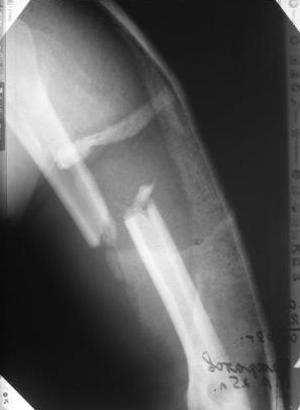

Какие Вам нужны конкретные ситуации... ведь диагноз есть, Р-снимки представлены... я выссказал свое мнение относительно штифтования... это и так предусматривает что у нас есть достаточное оснащение для этого ... какие еще ситуации нужны... наличие денег у пациента? или что???

Уважаемый товарисч.Данный перелом можно вылечить антероградным, ретроградным штифтованием, пластиной, аппаратом внешней фиксации, вытяжением за локтевой отросток на шине ЦИТО. Учитывая наличие тяжелой ЧМТ предпочтение должно отдаваться минимальноинвазивной технике.

Качество паредставленных Вами рентгеновских снимков крайне низкое, что косвенно свидетельствует об общей культуре работы в Вашем отделении.

Спасибо Алексей! Я и планировал провести антеградное штифтование но меня смущал относительно небольшой дистальный отломок. Может для кого-то данные вопросы и кажутся пустяком...но я только недавно начал использовать в своей работе штифты преимущественно Synthes. Еще раз спасибо

В том-то и беда, что Вы не задаете те вопросы, которые бы следовало задать, если предстоит не сильно знакомая операция антеградного остеосинтеза довольно дистального перелома плеча.

Давайте я Вам задам несколько вопросов. Какой гвоздь будуете использовать - производитель, длина, диаметр? Будете ли рассверливать канал? Чем, до какого диаметра? Как будете делать репозицию - на руках, дистрактор? Как будете запирать стержень в дистальном отломке - направление, количество винтов?

Всё правильно, просто я несколько разрозненно пытался сказать на частных примерах, то , что Вы систематизировали. Совершенно верно данный перелом можно и так и эдак, наиболее оптимально антеградное штифтование, хотя я бы предпочёл пластину LCP(просто - ну лучше у меня это получается и всё, а больному не вредит тот же функциональный способ). А низковато для неблокированного штифтования с конструкциями с термомеханической памятью, то, что представленно на втором снимке.